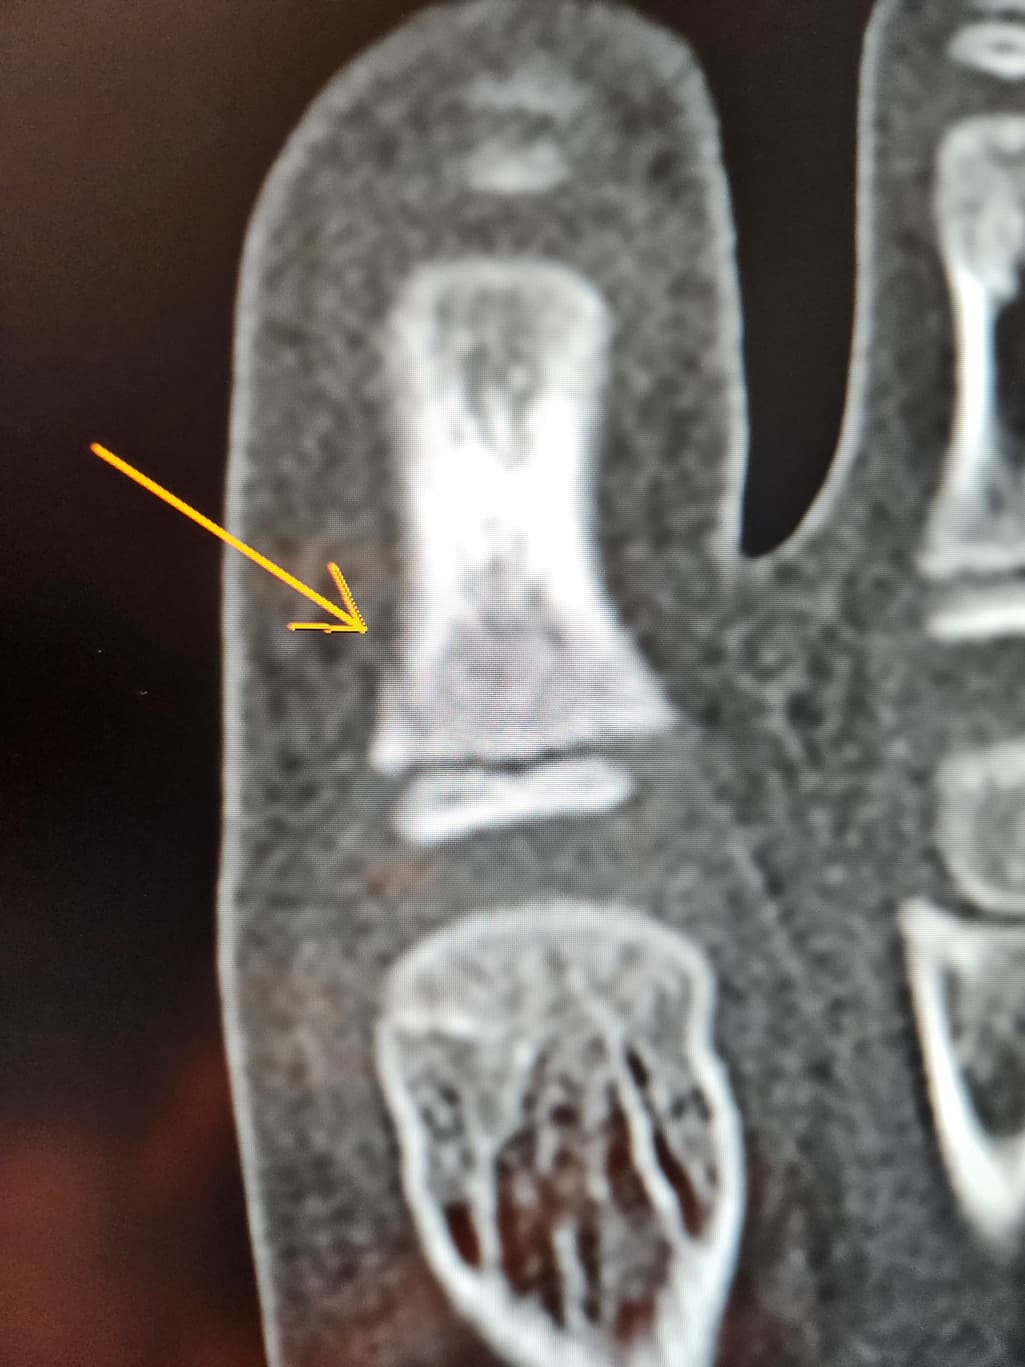

첫번째 사진은 엑스레이

두번째 세번째는 ct입니다

8세남아 맨바닥에서 축구하다가 땅을 찼어요ㅠ

수술하자하는데 제가 일주일만 경과보고프다해서 일단 통깁스만했는데ㅠ

핀 수술이 필요할까요?ㅠ